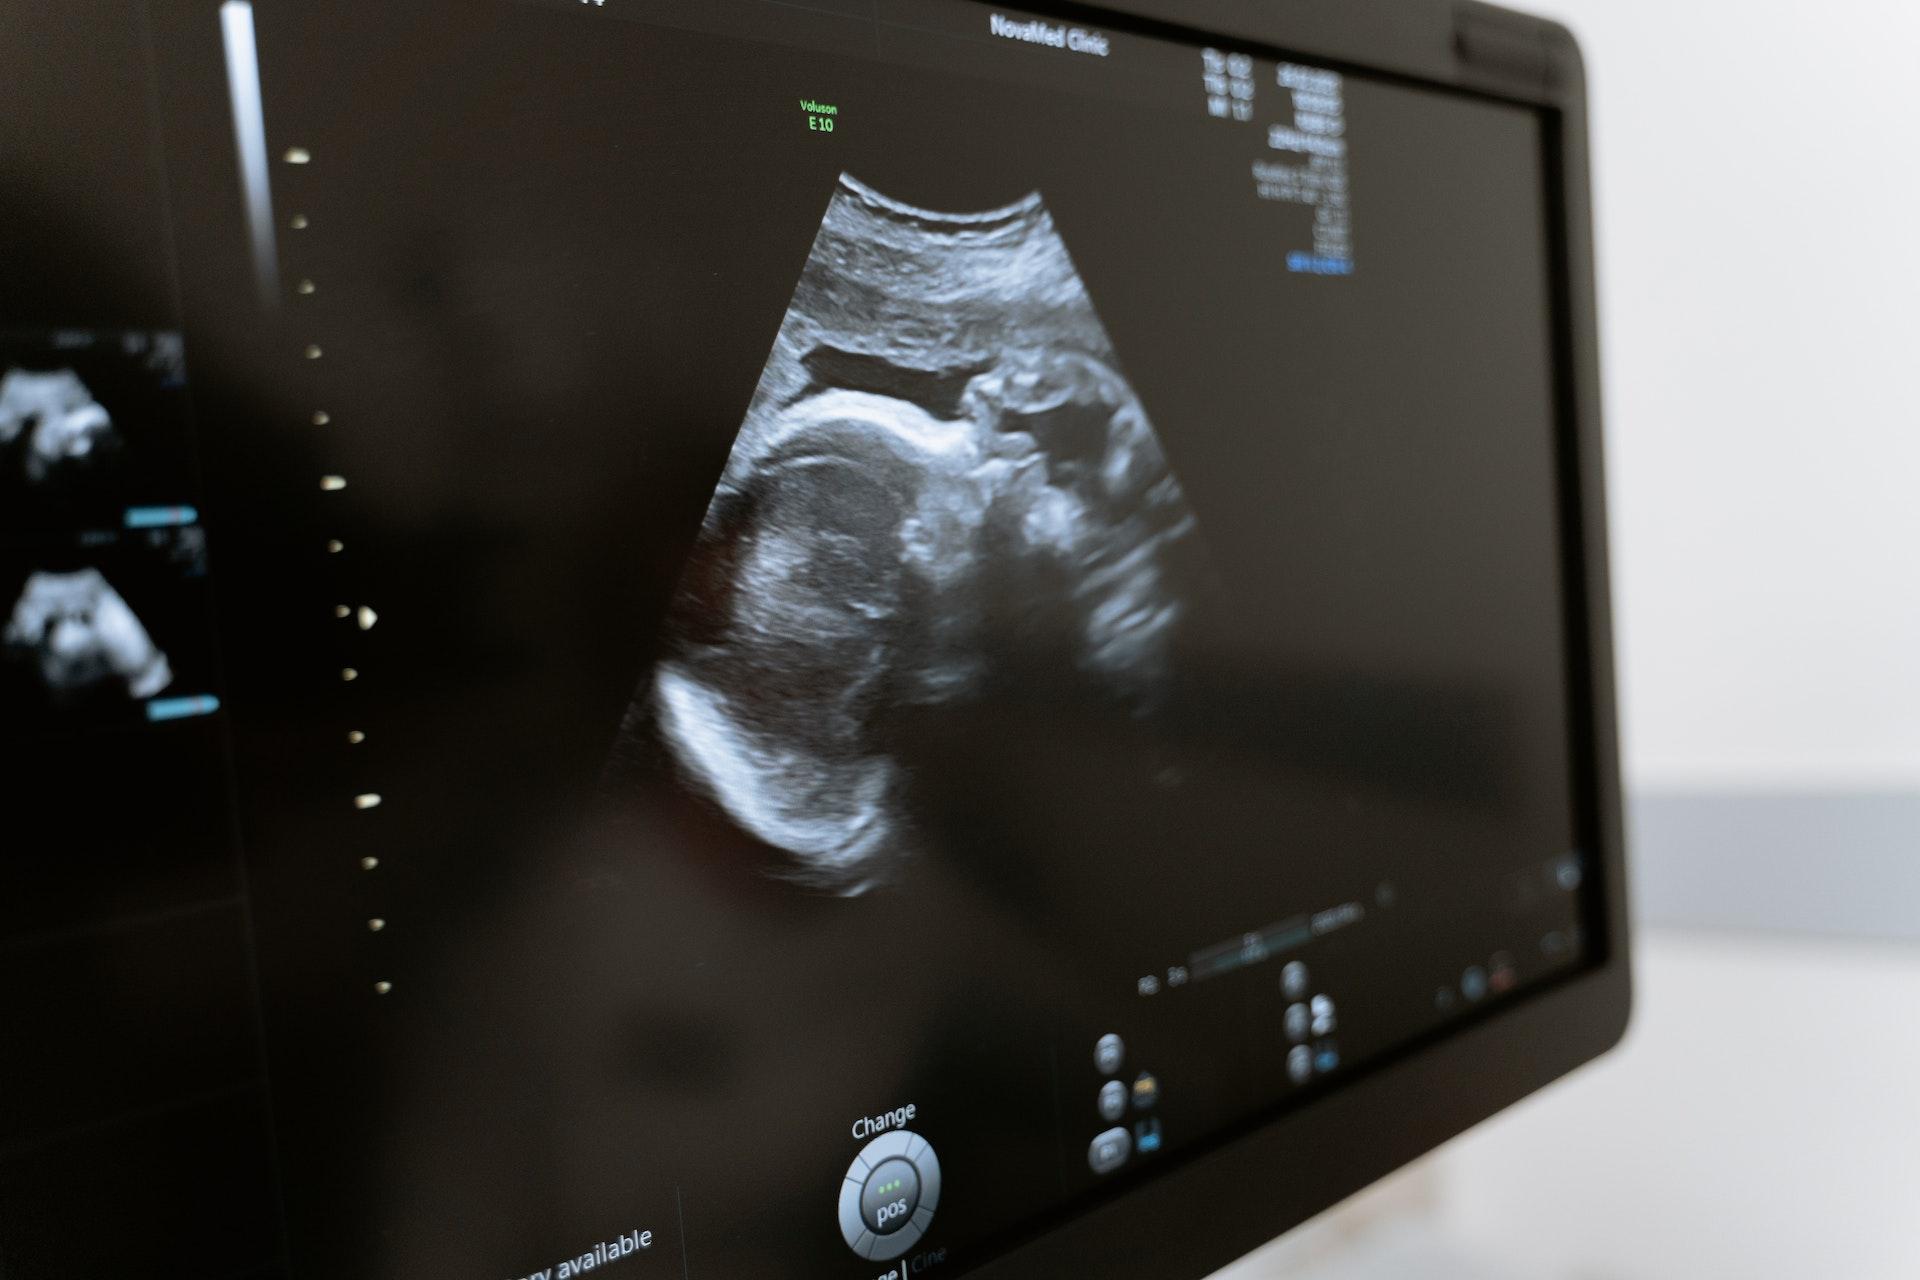

ultrazvuk | Pexels / MART PRODUCTION, Licence Pexels, ©

„Víc než dřív mohou teď ženy využít možnost, že potom, co dítě v rané fázi těhotenství odejde, nejdou do nemocnice na instrumentální revizi a čekají na spontánní potrat. Znám ale i ženu, která zažila obě varianty, v nemocnici i doma, a obě byly špatně. Za mě to bylo tím, že neměla vedle sebe oporu. I k potratu, stejně jako k porodu, je třeba mít někoho, o koho se budeme moct opřít. Ať už je to pátý týden, nebo čtyřicátý,“ říká o zkušenosti s potratem Alžběta Samková.